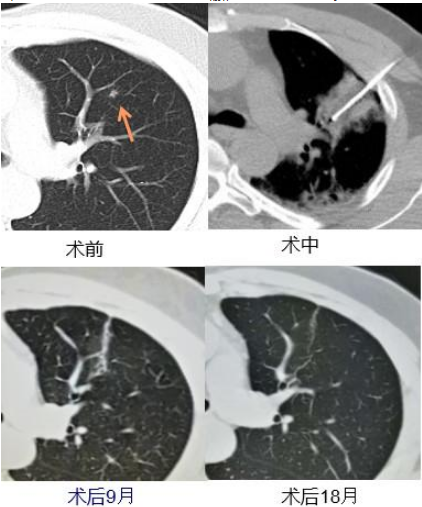

2015年,一位66岁老人因为左上肺有一处0.8*0.6厘米的肺部磨玻璃样变结节。由于患者年龄较大,不符合传统手术条件。在广州复大医院牛立志教授运用冷冻微创消融技术为患者治疗,无需开刀,通过针尖形成冰球把病灶消融,达到根治目的。术后一个月CT复查发现,病灶完全消融,至今无复发。

2018年,在广州复大医院牛立志教授为一名来自香港的80岁肺小结节患者做了冷冻微创消融术,患者原本以为要切除右肺,却不曾想伤口只有针眼般大小,达到与手术相同的根治效果,老人至今仍然健康生活。